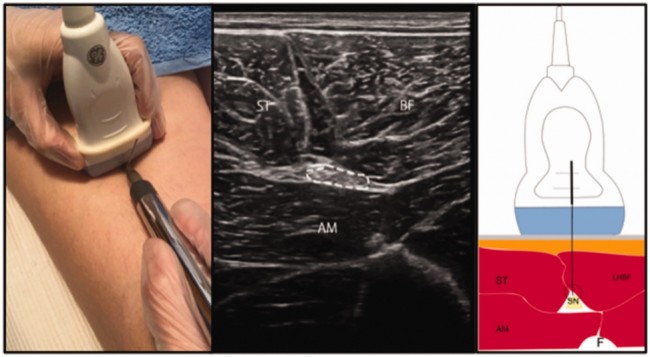

© Acupunct Med Figure 1. Ultrasound (US)-guided percutaneous neuromodulation (PNM). Left panel: photograph of PNM intervention on the sciatic nerve. Middle panel: US image of the intervention. Right panel: US-guided invasive approach to the sciatic nerve. Source: Adapted from Valera-Garrido and Minaya-Muñoz. ST: semitendinosus muscle; BF: biceps femoris muscle; AM: adductor magnus muscle; SN: sciatic nerve; F: femur. 4. 서지사항 분야 및 용도 부인과 - 다낭성 난소 증후군 진단 및 임신 추적 연구 요약 다낭성 난소 증후군 환자에서 침과 클로미펜의 효과 비교 초음파 활용 "초음파는 다낭성 난소 증후군의 진단 및 임신 후 2주에 1회 태아 심박동이 보일 때까지 추적하는 데 활용" 5. 서지사항 분야 및 용도 종양 – 중재 효과 평가 연구 요약 자궁내막암 환자에서 한약과 양약 병용 치료와 양약 단독 치료의 비교 초음파 활용 "자궁내막 형태, 자궁 내 병변 형태, 크기, 내부 에코, 근육층 침윤 깊이를 주의 깊게 관찰하기 위해 질 초음파를 정기적으로 시행" "칼라도플러플로우 모드를 사용하여 병변 부위의 혈류 관찰 및 혈액 저항지수 값 측정" 6. 서지사항 분야 및 용도 한의 임상 전반 - 진단 및 중재 효과 평가 연구 요약 한의학에서 초음파의 임상 활용에 관한 고찰 초음파 활용 "고찰에 포함된 46편의 연구 중 한의사가 초음파를 사용한 연구는 28%" "혈류 변화 관찰 (15편), 관절/근육 관련 (12편), 복부 관찰 (15편)에 초음파를 활용"